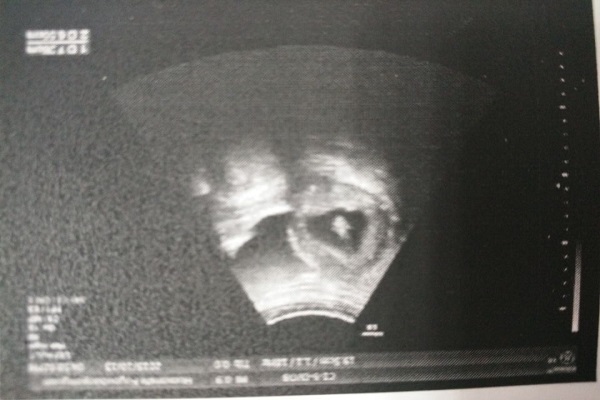

阴式B超真的有那么可怕吗?可能是你误解了,今天就来带大家了解一下两种B超的特点和区别。

能提前发现早早孕

对比之后可以发现,二者检查的方式不同,准确率也不同,相比之下前者更具优势,如果是宫外孕、瘢痕妊娠这种特殊情况,是不可能有时间憋尿的,普通B超太慢了,为了保障母婴安全,快速做出诊断,还是做阴超比较合适。

探头进入体内一般在4厘米左右,触及不到宫腔,离胎儿还有一定距离,所以孕妇也能做,而且它也没有辐射,不用担心致畸,非常安全。有的人做完检查发现*裤内**有血迹,怀疑是检查导致的,其实不能这么说,因为有的女性体质弱,胚胎发育不好,本来就有一定危险性,做阴超反而能帮助你尽早发现胚胎异常状况。